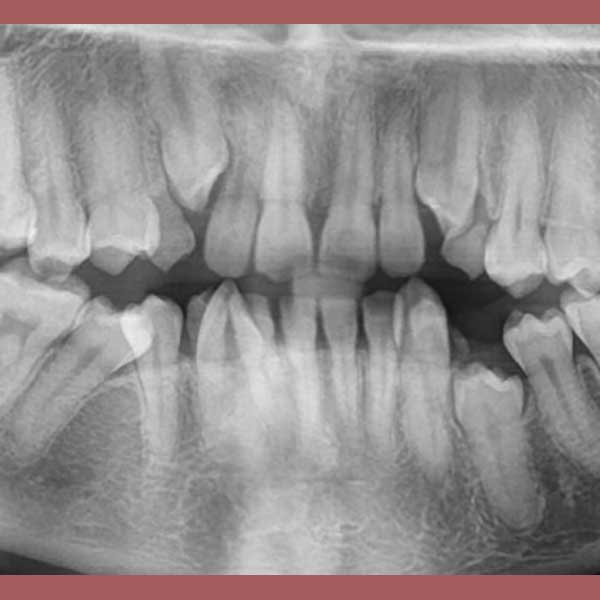

بعد الفحص وأخذ الصور الشعاعية، أوضح الدكتور خالد الكاتب أن الأنياب العلوية موجودة ولكنها منطمرة بالكامل في عظم الفك، بالإضافة لوجود ضاحك سفلي منطمر أيضاً. وبسبب كبر سن المريضة، كان لا بد من خطة علاج متكاملة: